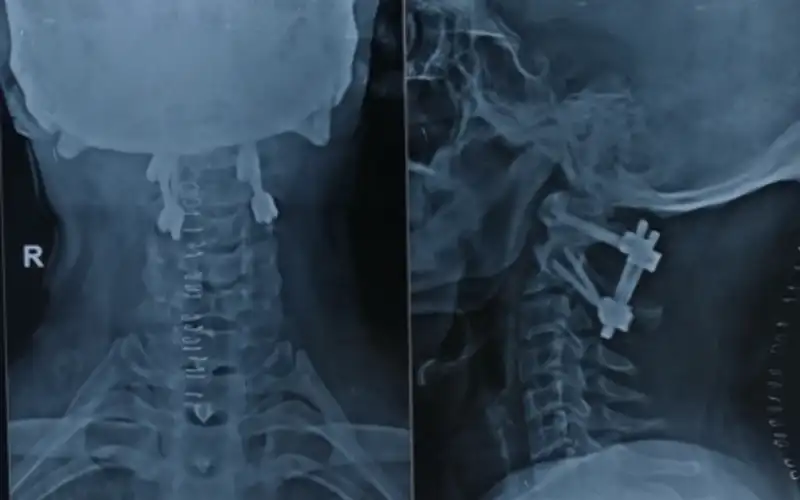

Minimally invasive C1-C2 fusion

C1-C2 instability Post OP X ray

C1-C2 fusion Post OP X ray